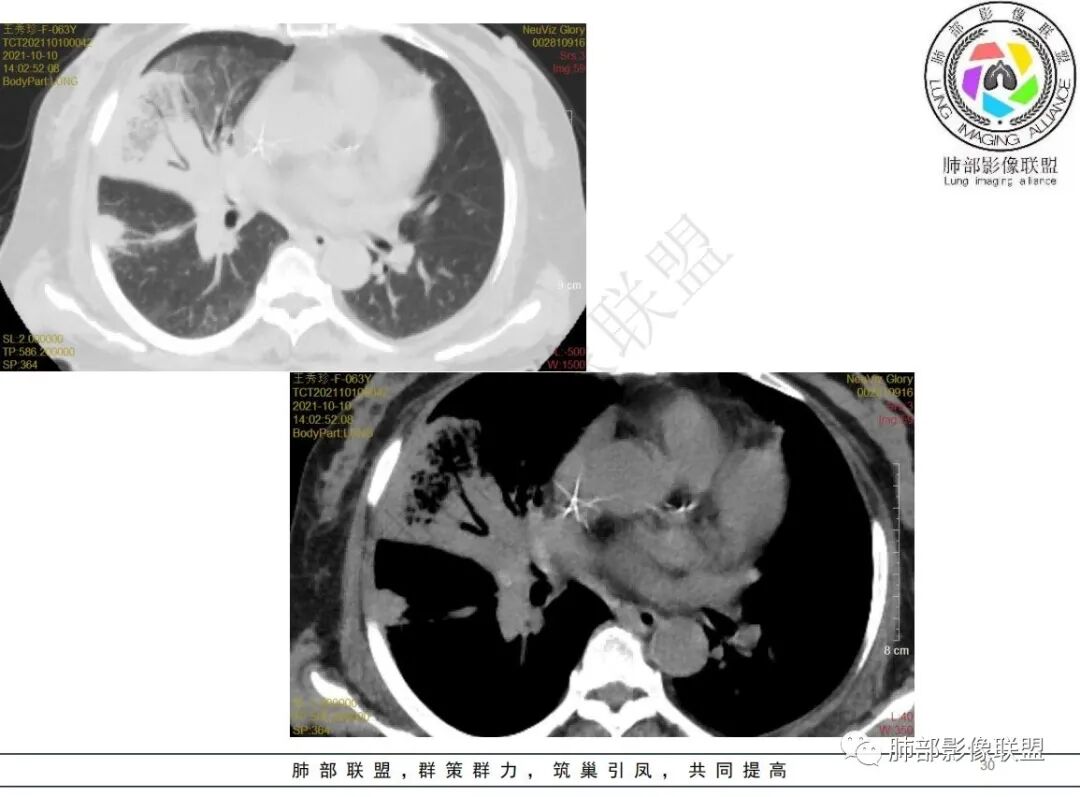

白血病化疗后,出现多发结节,边缘可见晕征,病灶内可见多发坏死,右肺中叶肺动脉可见充盈缺损,右肺中叶可见融冰征,考虑毛霉菌,右肺中叶肺动脉栓塞伴右肺中叶肺梗死。

4.白血病化疗后,CT上出现多发结节,边缘可见晕征,病灶内可见多发坏死,右肺中叶肺动脉可见充盈缺损,右肺中叶可见融冰征,右肺中叶肺动脉侵犯栓塞伴右肺中叶肺梗死,可符合真菌感染。

血管侵袭性曲霉病是最常见的类型,其特征是真菌菌丝侵入和阻塞中小肺动脉,形成凝固性坏死、肺泡出血或出血性梗死。

6.肺曲霉病典型的CT表现是结节周围有磨玻璃样的晕征表现,或胸膜为宽基底的楔形实变。晕征表现为曲菌感染的肺结节伴梗死和凝固性坏死,周围有肺泡出血。最终可出现空泡征象,并可观察到中央坏死组织与周围肺实质分离形成空气新月征。

晕征已被认为是侵袭性曲菌病的早期征象之一。